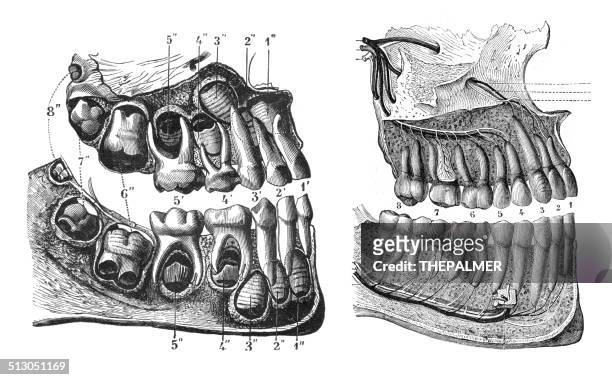

Discover the sophistication of annotated illustration of the jaw's anatomy | stable diffusion online with our curated gallery of numerous images. featuring elegant examples of photography, images, and pictures. ideal for luxury lifestyle publications. Browse our premium annotated illustration of the jaw's anatomy | stable diffusion online gallery featuring professionally curated photographs. Suitable for various applications including web design, social media, personal projects, and digital content creation All annotated illustration of the jaw's anatomy | stable diffusion online images are available in high resolution with professional-grade quality, optimized for both digital and print applications, and include comprehensive metadata for easy organization and usage. Our annotated illustration of the jaw's anatomy | stable diffusion online gallery offers diverse visual resources to bring your ideas to life. Professional licensing options accommodate both commercial and educational usage requirements. Cost-effective licensing makes professional annotated illustration of the jaw's anatomy | stable diffusion online photography accessible to all budgets. Regular updates keep the annotated illustration of the jaw's anatomy | stable diffusion online collection current with contemporary trends and styles. Multiple resolution options ensure optimal performance across different platforms and applications. Time-saving browsing features help users locate ideal annotated illustration of the jaw's anatomy | stable diffusion online images quickly. Whether for commercial projects or personal use, our annotated illustration of the jaw's anatomy | stable diffusion online collection delivers consistent excellence.